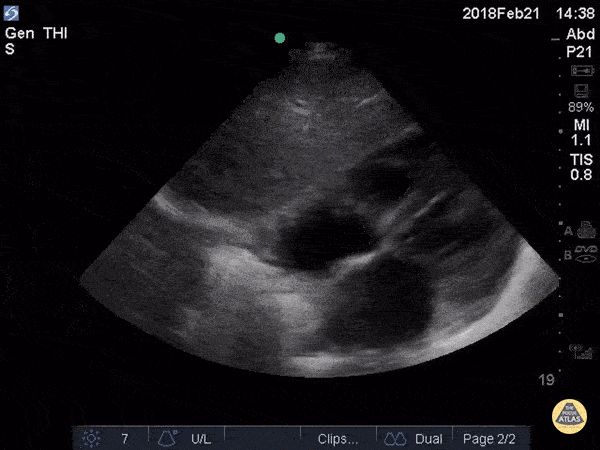

Which LUQ view represents a positive FAST (fluid present)?

The correct answer is A. Free fluid can be visualized between the diaphragm at the left side of the screen and the spleen on the right.